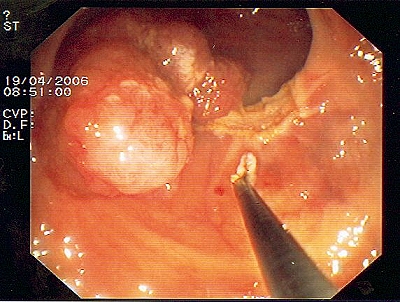

Großer Polyp des Dickdarmes

Wie bei den Abbildungen 28 und 30 handelt es sich um einen breitbasigen, relativ flachen, noch nicht entarteten Polyp, der sich mit einer Schlinge nicht vollständig abtragen ließe.